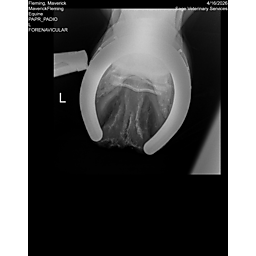

**Maverick sells at the Colorado Horse Sale’s Best of the West Select Sale on May 30th in Castle Rock, CO - He will complete the riding & handling Sift Exam, baseline veterinary exam, and will sell with 4 total radiographs (DLPMO & Front Foot Lateral)**